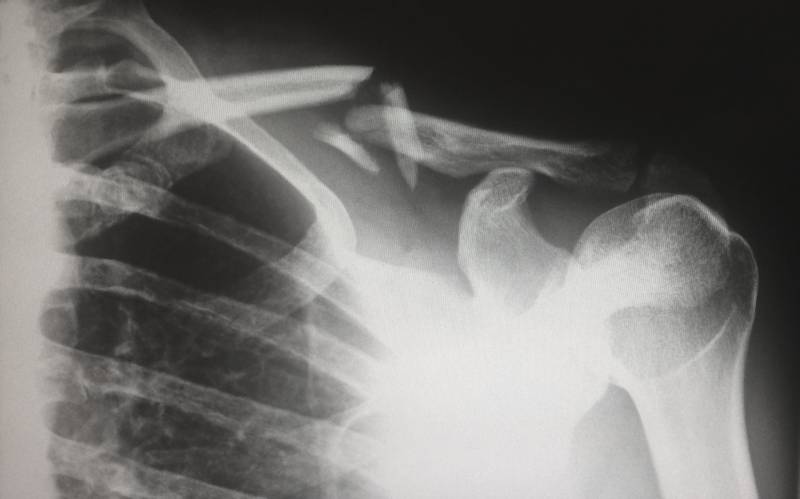

Exemple de réparation suite à agression

Monsieur H., buraliste, a été victime d'une agression alors qu'il se rendait à la banque pour déposer sa recette. Un individu lui a tiré dessus avec une arme à balle caoutchouc et il a été blessé à la jambe. L'agresseur s'est...